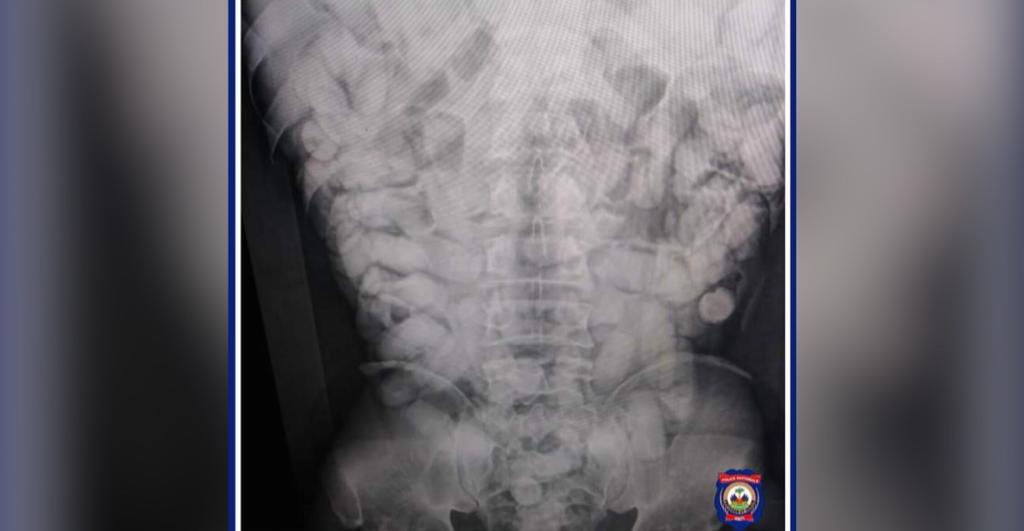

Suspecté de transporter dans son abdomen des corps étranges, l’individu qui se trouvait à bord d’un vol en direction de Paris a été conduit à l’hôpital Bernard Mevs pour des examens plus poussé.

À la suite d’une radiographie révélant la présence de corps étranger s’apparentant à de la drogue une procédure de récupération de ces corps a été entamée.

Le constat fait état d’un total de 1,35 Kg de cocaïne divisée en 102 bâtonnets de drogue récupérés dans l’intestin du nommé IK EGBOR.